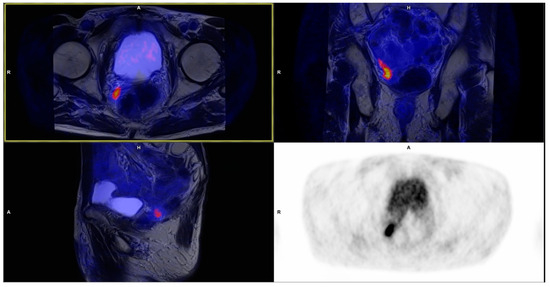

3.1. Local Recurrence

3.2. Lymph Nodes

| Recurrence Site | No. of Detected Lesions | Mean SUVmax ± SD | Size Range (mm) |

|---|---|---|---|

| Prostatic bed | 13 | 6.34 ± 2.53 | 6 × 4 up to 19 × 18 × 25 |

| Pelvic lymph nodes | 34 | 5.46 ± 3.28 | 3 × 3 up to 11 × 11 |

| Extrapelvic lymph nodes | 1 * | 3.75 | 3 × 3 |

| Bones | 5 | 4.75 ± 1.82 | 5 × 4 up to 8 × 8 |